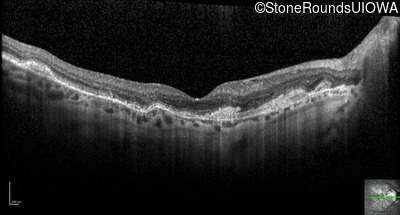

Optical Coherence Tomography - Right - 20/25 +1

Exemplar / OCT Stack